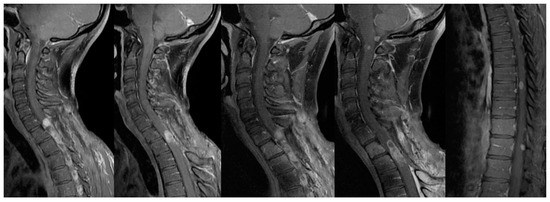

3.2. Unexpected Radiological Features in a Case of SpDG H3K27M

4.2. Radiological Finding